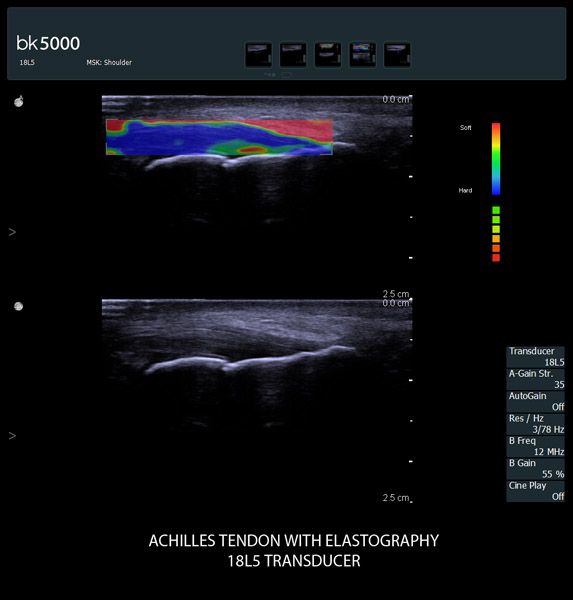

Addressing Challenges with Advanced Technologies

From the simplest diagnostic imaging to the most critical interventional procedures, every clinical situation has its own set of unique challenges. The bk5000 offers a full suite of innovative technologies and advanced controls and adjustments to help you achieve the best possible image quality, across many applications.